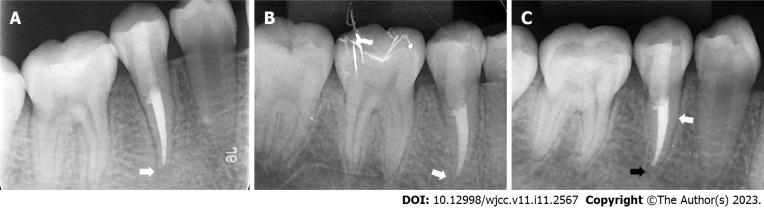

A 10-year-old girl complained of pain in the right upper and lower posterior teeth for 2 d. Clinical and radiological examinations revealed that both the right maxillary and mandibular second premolars were immature with periapical radiolucency. The right maxillary second premolar was treated by pulp revascularization, while the right mandibular second premolar was treated by conventional apical barrier surgery after revascularization failed. The purpose of this report is to compare the different root maturation processes induced by the pulp revascularization and apical barrier techniques in the same patient in homonymous teeth from different jaws. Twelve months of follow-up showed that the apical foramen of both teeth presented a clear tendency to close; however, the tooth treated with pulp revascularization showed a significant increase in root length as well as root canal wall thickness.

For the treatment of nonvital immature teeth, pulp revascularization showed a superior therapeutic effect in comparison with the apical barrier technique.